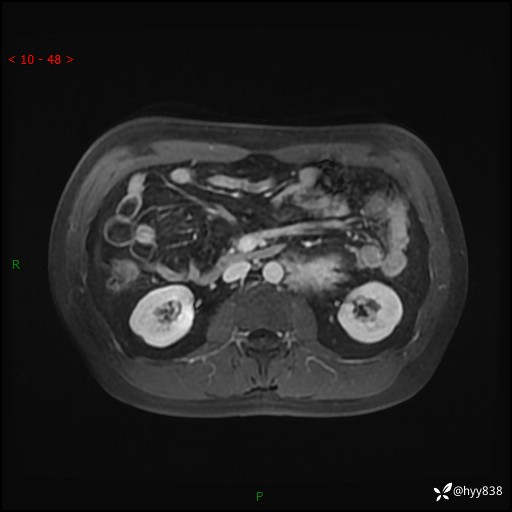

MRI增强